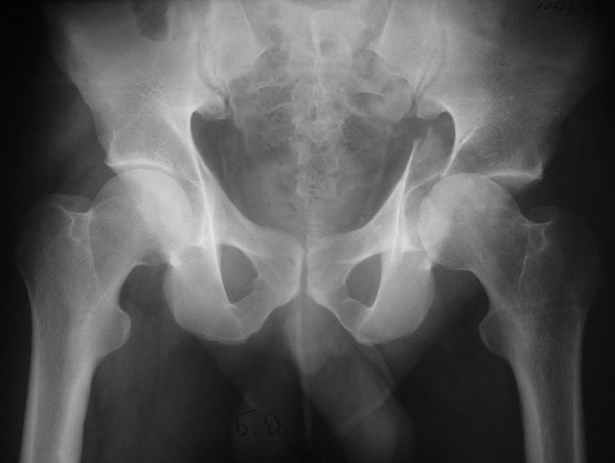

Anatoly F Lazarev 03 Сентябрь 2004, 22:39

Высылаю пример еще одного случая, остеосинтез пластиной из подвздошного доступа.